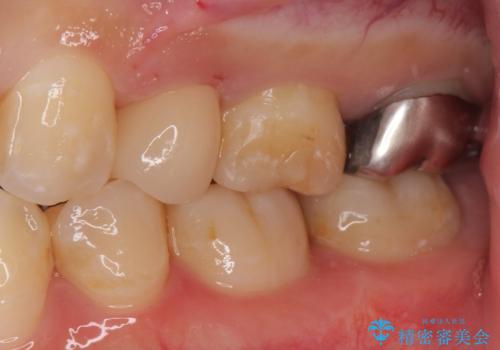

白くて適合の良い被せ物が入りました。

セラミックは劣化することがなく虫歯の再発のリスクが低くなります。